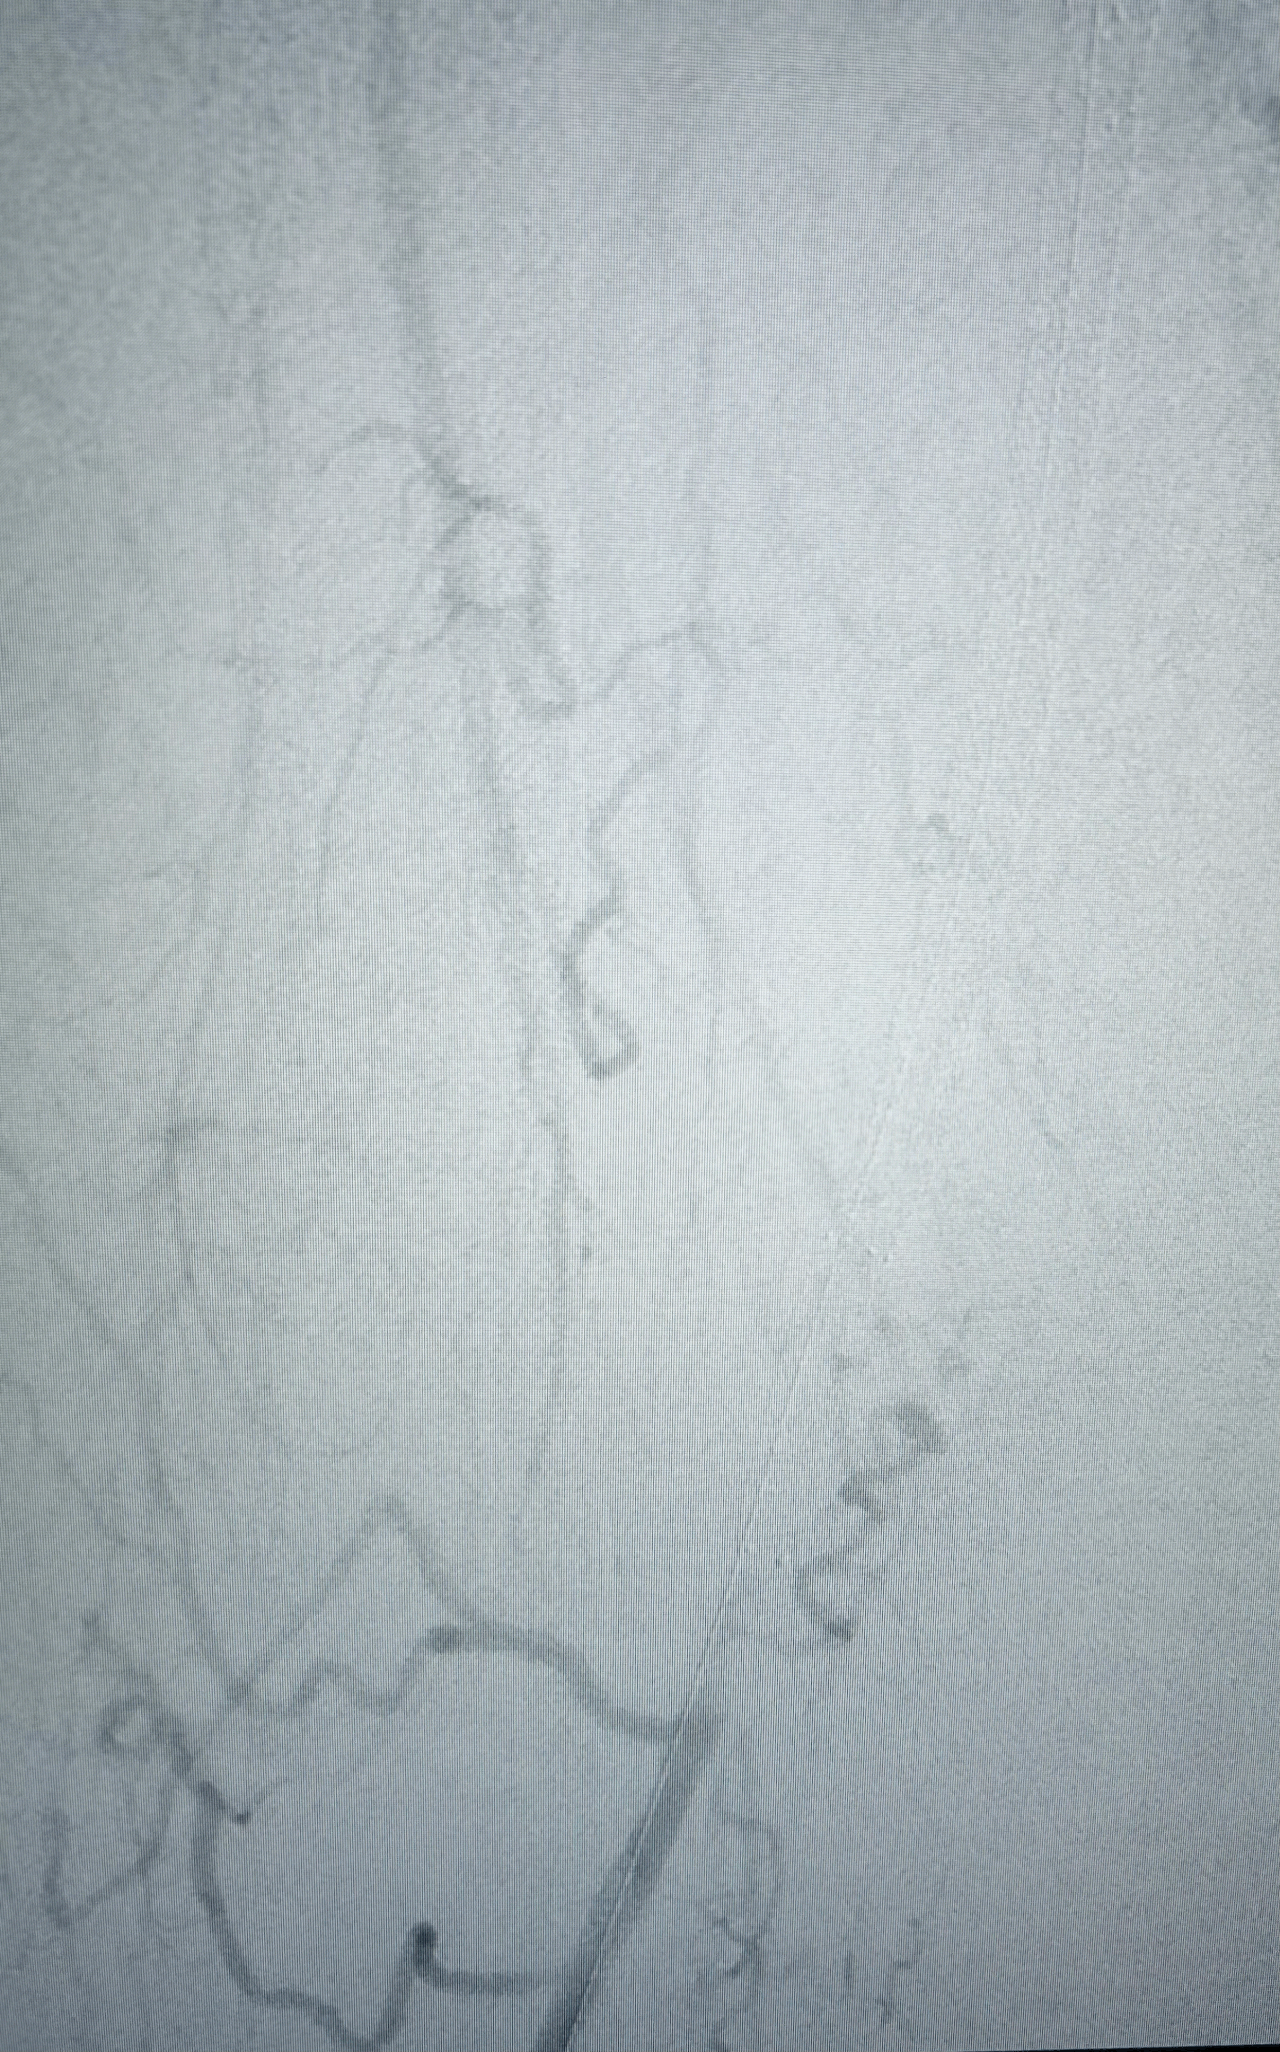

Athérectomie endovasculaire

Préparation artérielle avant angioplastie par retrait ciblé de plaque d’athérome

Principe

L’athérectomie endovasculaire est une technique mini-invasive permettant de préparer une artère avant une angioplastie par ballonnet. Elle consiste à retirer de manière ciblée la plaque d’athérome, notamment calcifiée, à l’aide de sondes spécifiques - sorte de "foreuse" - introduites par voie endovasculaire, sans ouverture chirurgicale de l’artère.

Indications

Cette technique permet de traiter des localisations artérielles complexes qui nécessitaient auparavant un abord chirurgical direct, en particulier :

• le trépied fémoral au pli de l’aine,

• l’artère poplitée en région rétro-articulaire.

Intérêt thérapeutique

En retirant la plaque d’athérome calcifiée, l’athérectomie permet dans de nombreux cas d’éviter la mise en place d’un stent dans des zones de flexion. Ces zones sont soumises à d’importantes contraintes mécaniques, exposant les stents à un risque de fracture et de thrombose secondaire.

Cette stratégie peut ainsi permettre d’éviter une revascularisation chirurgicale plus lourde, telle qu’un pontage artériel ou une endartériectomie par abord direct.